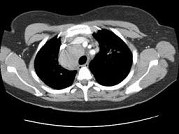

单项选择题女,33岁, 咳嗽,无发热, 结合图像,最可能的诊断是 ( )

A、肺结节病

B、淋巴瘤

C、中央型肺癌

D、胸腺瘤

E、支气管囊肿